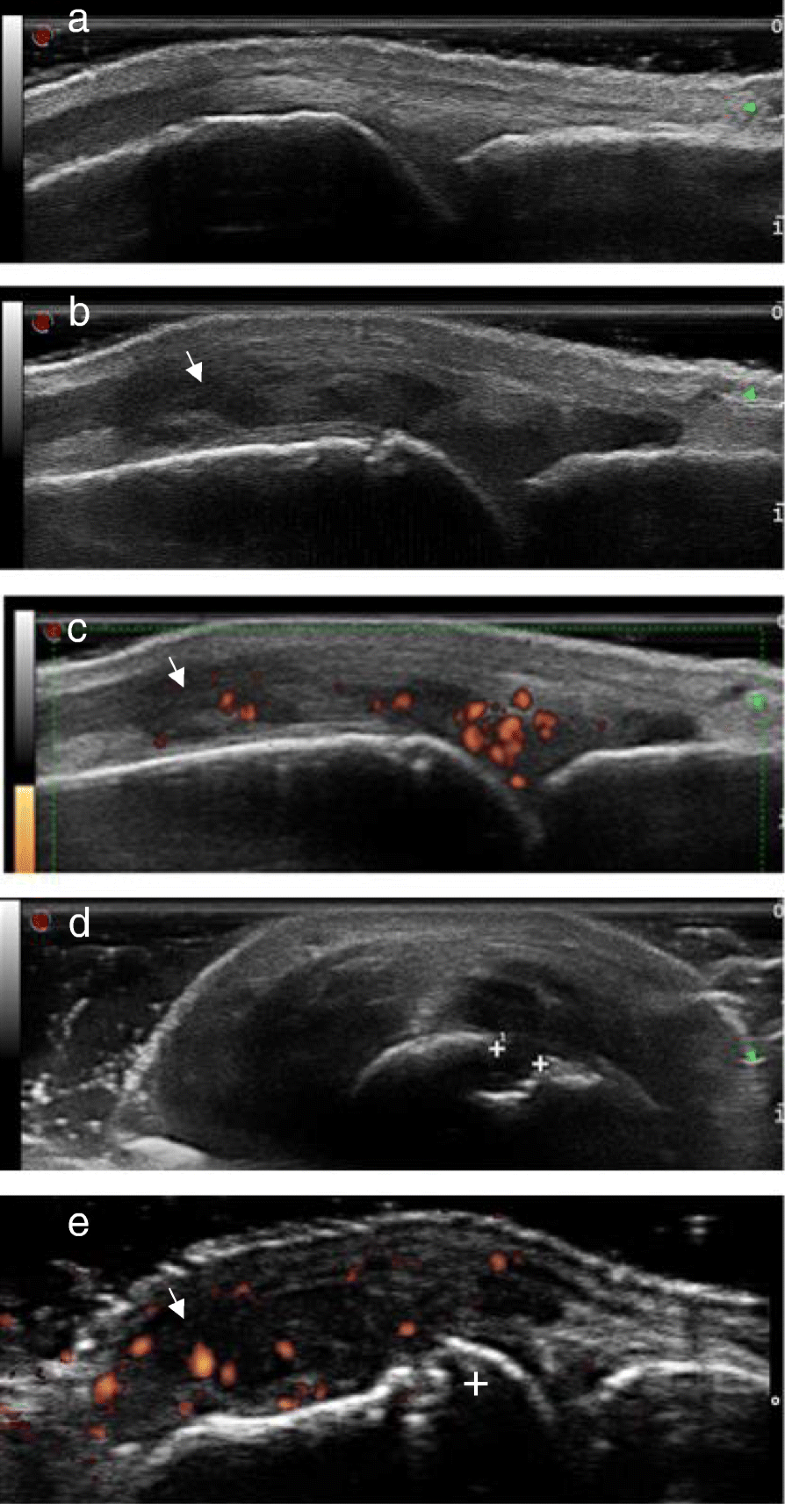

(PDF) Changes of inflammation in patients with psoriatic arthritis Inflammatory Arthritis Ultrasound In the presence of joint space narrowing, it is important to differentiate inflammatory from degenerative conditions. Developments and improvements in knowledge are rapid and ongoing in both the radiologic and rheumatologic fields. Consequently, imaging—especially ultrasound—is now an essential part of early inflammatory arthritis diagnosis and differentiation, and its. Imaging techniques such as ultrasonography and mri have gained ground in the. Inflammatory Arthritis Ultrasound.

Inflammatory tenosynovitis in a patient with known rheumatoid arthritis Inflammatory Arthritis Ultrasound Developments and improvements in knowledge are rapid and ongoing in both the radiologic and rheumatologic fields. Consequently, imaging—especially ultrasound—is now an essential part of early inflammatory arthritis diagnosis and differentiation, and its. Imaging techniques such as ultrasonography and mri have gained ground in the diagnosis and management of inflammatory. In the presence of joint space narrowing, it is important to. Inflammatory Arthritis Ultrasound.

Rheumatoid arthritis. Power Doppler images of a second... Download Inflammatory Arthritis Ultrasound Developments and improvements in knowledge are rapid and ongoing in both the radiologic and rheumatologic fields. Consequently, imaging—especially ultrasound—is now an essential part of early inflammatory arthritis diagnosis and differentiation, and its. Imaging techniques such as ultrasonography and mri have gained ground in the diagnosis and management of inflammatory. With effective treatment strategies for inflammatory arthropathies becoming extensively available,. In. Inflammatory Arthritis Ultrasound.

Figure 2 from Ultrasound in rheumatoid arthritis. Semantic Scholar Inflammatory Arthritis Ultrasound In the presence of joint space narrowing, it is important to differentiate inflammatory from degenerative conditions. Imaging techniques such as ultrasonography and mri have gained ground in the diagnosis and management of inflammatory. Developments and improvements in knowledge are rapid and ongoing in both the radiologic and rheumatologic fields. With effective treatment strategies for inflammatory arthropathies becoming extensively available,. Consequently,. Inflammatory Arthritis Ultrasound.